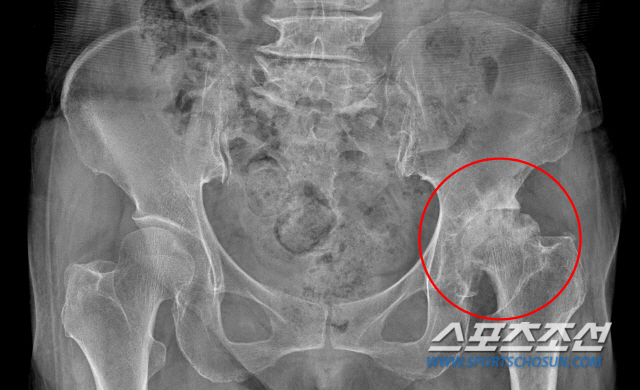

필자가 전문의가 되고 난 후 몇 년 지났을 때 내원한 환자가 지금도 기억이 생생하다. 그 환자는 1년 동안 소주 8병을 매일 마셨다고 한다. 지금은 소주가 16~18도 수준이지만 당시는 25도 정도였다. 그 독한 술을 밥은 안 먹고, 안주도 없이 마셨으니 간이 버텨낼 수가 없었다. 간은 응고된 피를 풀어주는 기능을 하는데, 간 기능이 떨어져 피가 응고되니 혈액순환이 안 돼 고관절에 피가 잘 공급이 안 되었고, 결국 괴사가 일어난 것이다.

환자는 양쪽 고관절 모두 인공관절 수술을 하고 다시 일상으로 돌아갔다. 질환의 주원인이었던 술도 끊었다. 하지만 1년 후 다시 술을 마신다는 이야기를 듣고 극구 말렸다. 술 때문에 그렇게 고생을 했는데도 왜 또 술을 마시는지 안타깝기도 하고, 화가 나기도 했다.